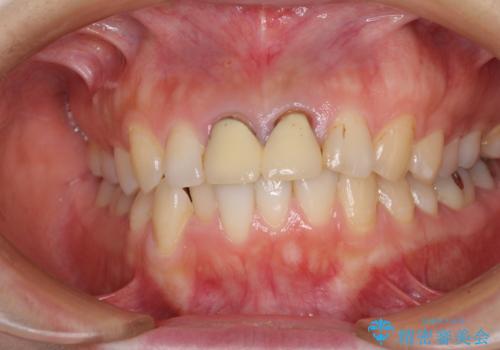

- 前歯のクラウンが着色により不自然な色となっていることを気にして来院された患者様です。

クラウンと歯の縁も合っておらず、汚れが溜まりやすい環境であったため、前歯2歯のクラウンをオールセラミッククラウンにて再補綴することとしました。

また、下顎前歯の叢生も気になっているとのことで、上顎の治療と並行して部分矯正を行うこととしました。